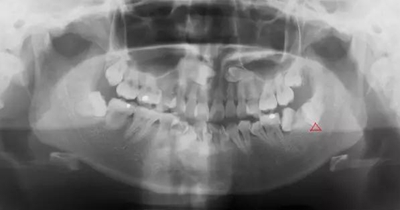

因正畸需要拔除智齒

3.jpg